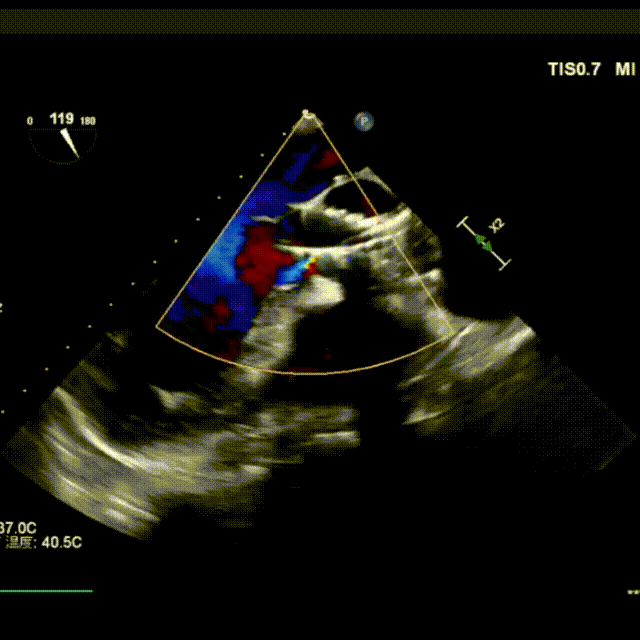

释放中期,快速起搏下释放到80%切换视图,并借助食管心超评估深度和反流情况:

超声复查,支架形态满意,手术结束: